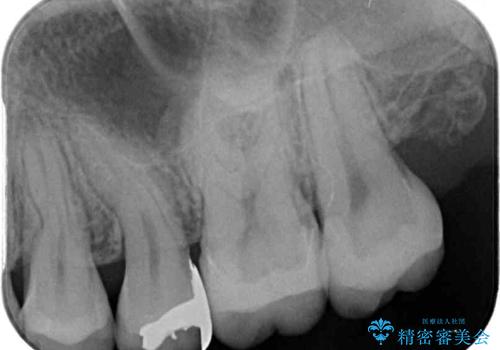

- 奥歯に頻繁に物が挟まるとのことで来院された患者様です。

最近ものが挟まりやすくなったり、冷たいものがしみるようになったりといった症状があり、診査したところ、むし歯や歯質の欠損、不適修復物などが認められました。

精度の高いセラミックインレーによる修復治療を行うこととしました。